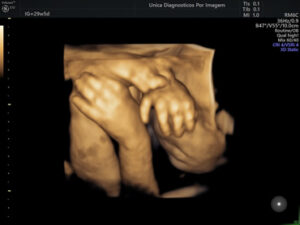

Exame importante que tem como objetivo avaliar a anatomia do feto e detectar possíveis malformações. Deve ser realizado preferencialmente realizado